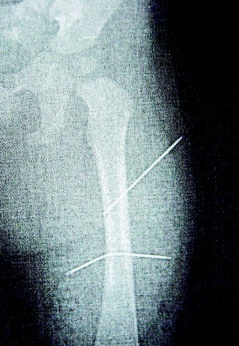

隔月27日,該女子又見(jiàn)外甥女哭鬧不停,拿蒼蠅拍朝著外甥女背部連打數(shù)十下,造成女娃背部瘀傷。經(jīng)女娃母親發(fā)現(xiàn)后送醫(yī)救護(hù),院方為女童進(jìn)行X光片照射后,才發(fā)現(xiàn)女娃左大腿里竟有兩根縫衣針。